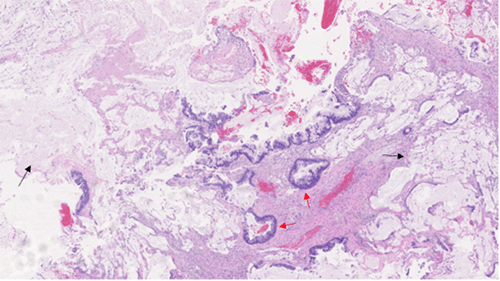

The patient completed a course of vancomycin for multifocal MRSA hospital-acquired pneumonia. Albendazole was discontinued after a lack of pathological evidence of echinococcal disease. The hospital course was complicated by a prolonged stay, liver injury, and respiratory failure requiring a tracheostomy and eventually discharge to a skilled nursing facility. The surgical specimen revealed a cystic mass with abundant tan-brown mucoid material, which was adherent to the inner lining of the cyst. Microscopically, the cyst consisted of abundant mucus-filled dilated spaces lined by atypical columnar cells confirming the diagnosis of invasive mucinous adenocarcinoma (Figure 3). Next-generation sequencing was performed on the tumor and revealed a KRAS p.Gly13Asp gain of function mutation confirming mucinous carcinoma. The patient was referred to the oncology outpatient clinic for systemic chemotherapy for presumed stage IV disease with gross spillage into the thoracic cavity.

Figure 3. Histopathology of Invasive Mucinous Adenocarcinoma at 4x Magnification. Published With Permission

Large mucin-filled spaces (black arrows) and infiltrative acini (red arrows).